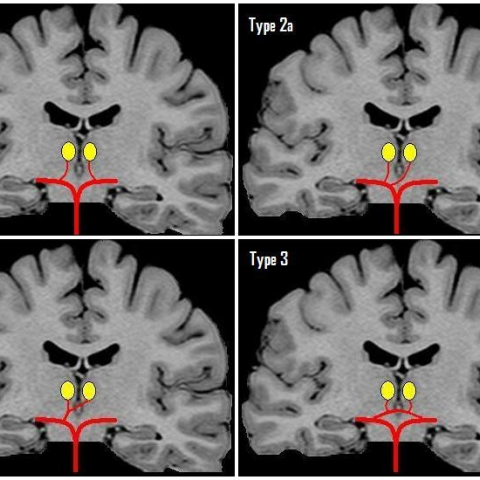

Infartos talámicos mediales bilaterales, un hallazgo típico debido a la oclusión de la arteria de Percheron